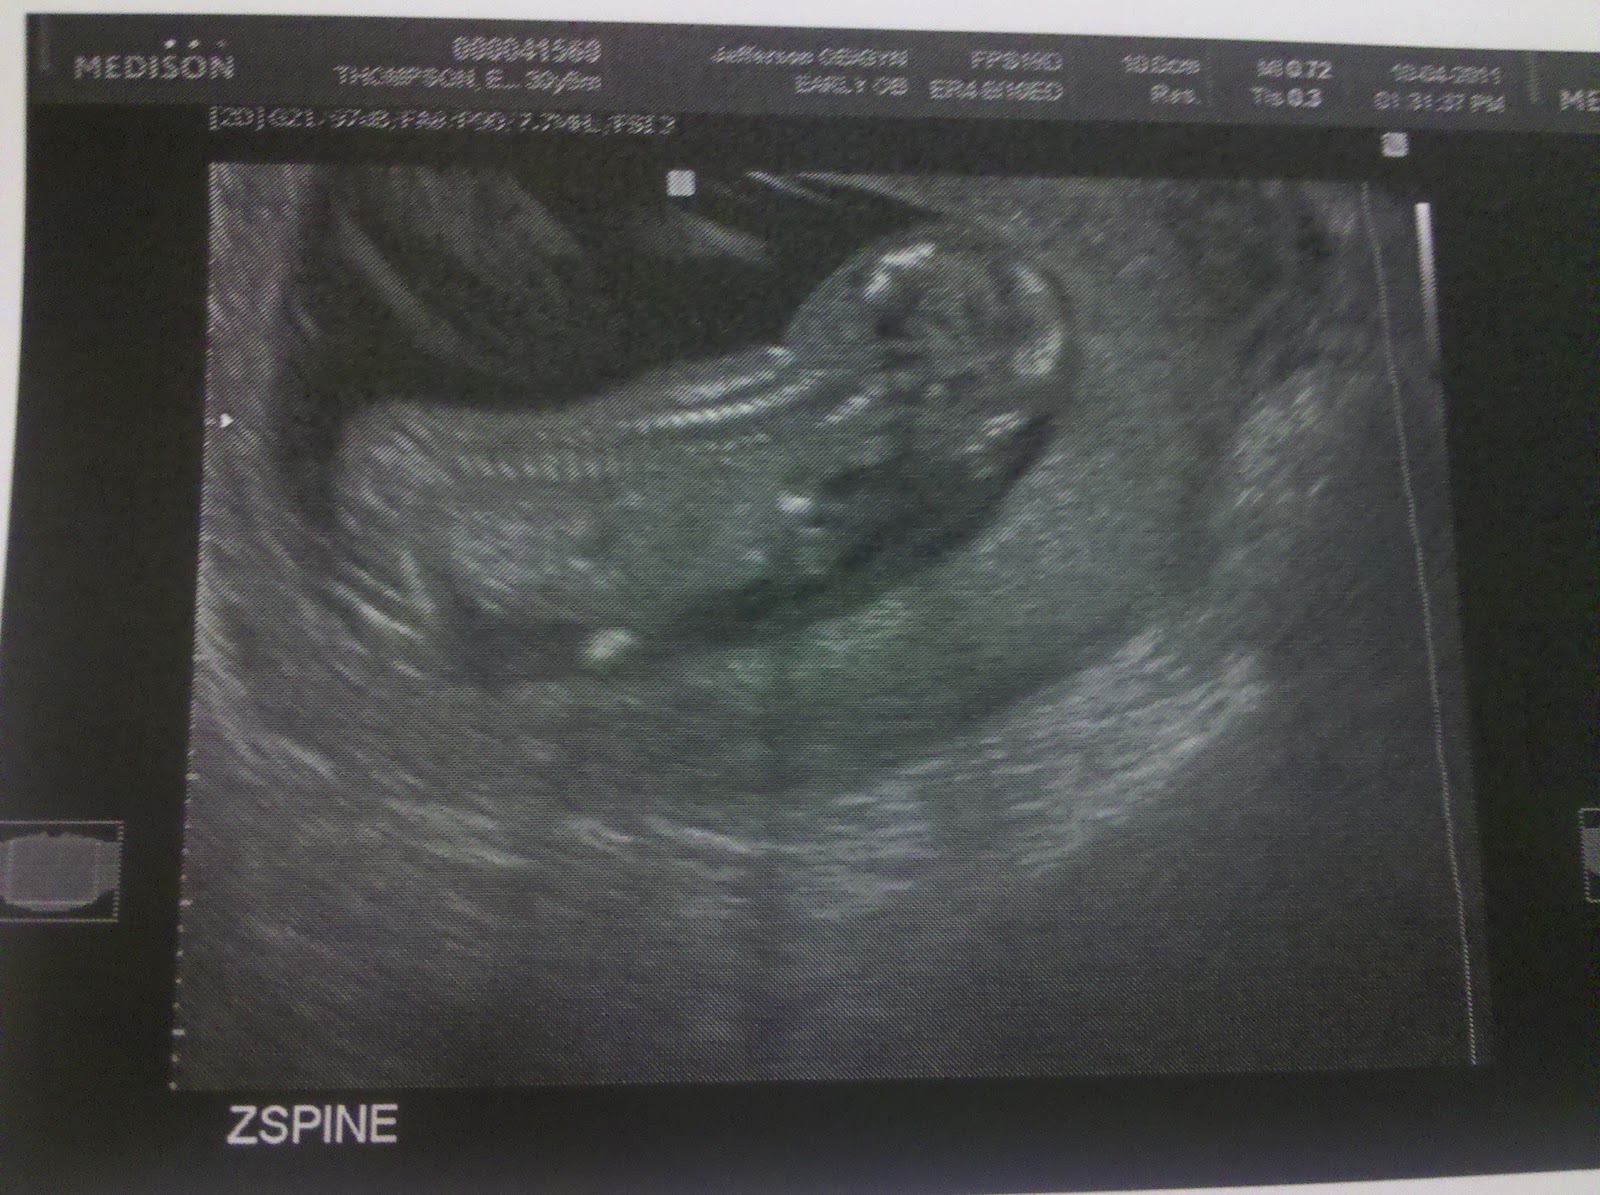

It's A...

BOY!!!!

22 weeks today and had our ultrasound. Baby Boy Thomson is a mover. He enjoys punching his mom continuously. He's breech, with plenty of time to turn! Estimated weight based on measurements is 1 lb., 1 oz. Arm and leg bones look normal, heart has 4 chambers with septal walls intact, bladder in good shape, and spinal cord looks good.

On a side note...we have placenta previa, type II marginal, which means the placenta is slightly covering my cervix. However we are having another ultrasound in 4 weeks to see if things have changed. Fingers crossed that they have or Baby T may have no choice but to be born via cesarean section and bedrest may be required.